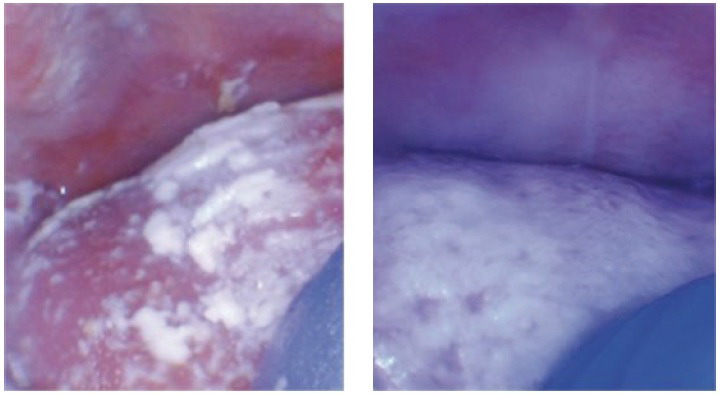

许多舌系带过短婴儿的舌背上会有一层白色的舌苔,因此而经常被误诊为鹅口疮。这种白色的舌苔(也叫奶苔)是由于舌休息时(低舌位)不接触上腭,残留的母乳不能被摩擦掉而形成的。婴儿的舌和成人一样,休息时应停靠在上腭表面,如果这些婴儿白色的舌苔只存在于舌背,那么不考虑为鹅口疮,而应高度怀疑舌活动受限。舌系带过短婴儿的另一个迹象是唇部的吮吸水疱或硬茧,这表明婴儿的吮吸功能不正常,婴儿是依赖唇而不是通过舌产生喝奶时的真空。此外,过度频繁打嗝(或在子宫内经常打嗝)的婴儿更有可能患有神经疾患导致的口腔系带问题,比如迷走神经和支配膈肌的膈神经发育不全。这是神经系统发育不全或失调的信号。

婴儿高拱的上腭和唇部的吸吮水疱

新生儿的鹅口疮(左)是厚实的,通常发生在颊部、上腭和舌。舌系带过短引起的舌苔为光滑的白色(右),位于舌体的后部。后者不需要治疗,通常在系带矫正手术后的几周内消失。